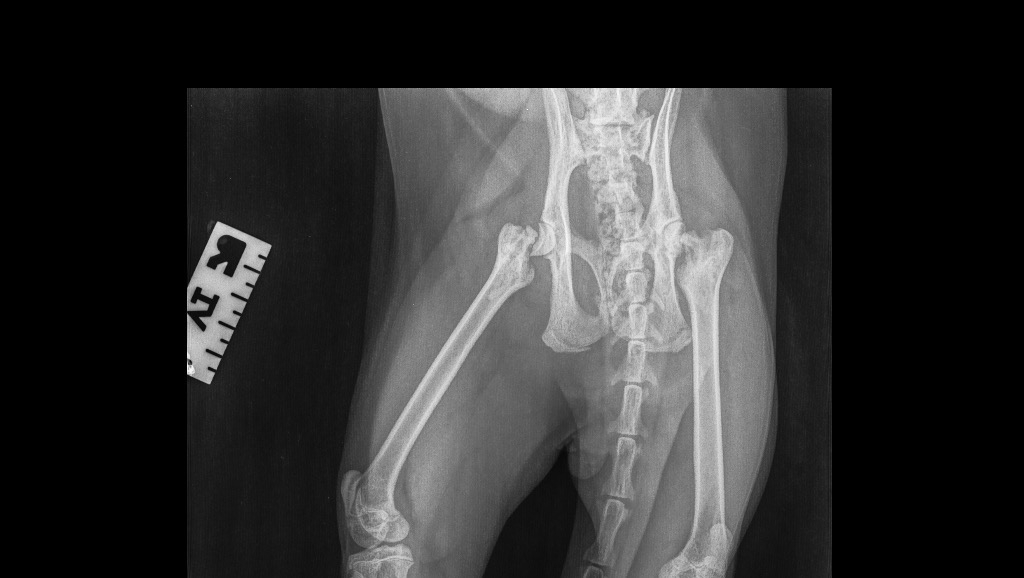

On the 26th of October our beautiful boy Kylo had an X-ray because he was limping. He must be one tough cat because the X-rays showed a serious condition. He had a snapped femur on one side and disintegrating bone in the opposite femur head. Our hearts broke. Our beautiful boy had never been outside, nor in any falls or accidents. How could he possibly have this much damage in his hips? The prognosis was poor. The affordable options for us were euthanasia or a life on pain medication which would result in kidney and liver damage as well as only offer a 25% chance of living pain free. This was not an option for us.

After doing some research and discussing with his vet we have discovered that Kylo has a rare degenerative disease called Legg-Perthes Disease which affects young cats (and dogs and humans). Only 12-16% of those diagnosed with the disease have it in both legs, like Kylo.

The other two options for Kylo, after receiving this diagnoses, included a total hip replacement which would be up to $20,000 per leg and just entirely out of our budget in any thinkable way. Instead, we have decided to go ahead with a femoral head and neck excision. He will need two surgeries to remove the head and neck of the femur, with his muscles and tendons taking over as a false joint. This surgery offers an 84-100% chance that he will live pain free and without further intervention. It is still an expensive surgery with our wonderful vet quoting $2105 for the first surgery and $1960 for the second surgery.